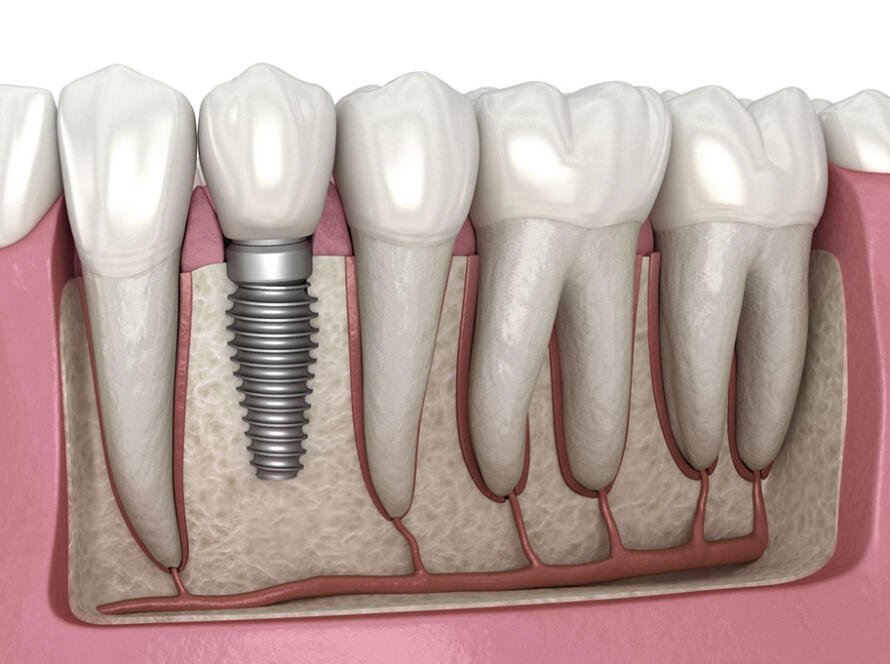

Choose the Right Tooth Implant for Permanent Tooth Replacement Tooth implants restore missing teeth with natural function and appearance through advanced dental implant treatment. Dental implants provide the gold standard in permanent…